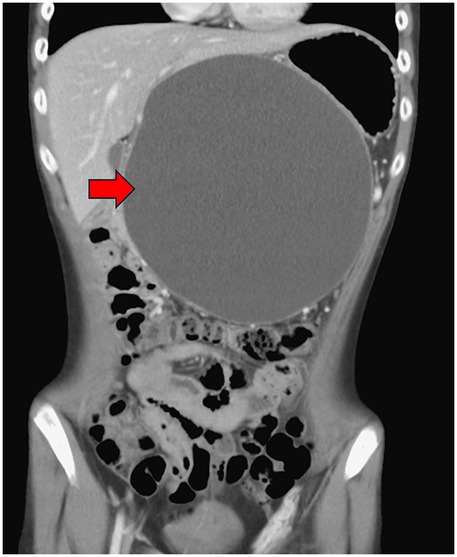

A 14-year and 6-month-old boy with a history of recurrent pancreatitis, ASD (with communication impairment), and learning disorder presented with frequent non-bilious vomiting for 1 day. Associated symptoms included epigastric fullness, nausea, left-lower quadrant abdominal pain, reduced activity, and decreased oral intake. His mother also reported a progressively enlarging epigastric mass. There was no fever, history of glucose-6-phosphate dehydrogenase deficiency, asthma, allergic rhinitis, or family history of autoimmune disease. On examination, the abdomen was protuberant with an ovoid, non-tender, mass-like lesion measuring approximately 10 cm × 10 cm, without rebound pain. Laboratory findings included serum glucose 107 mg/dL, lipase 155 U/L, and amylase 200 U/L. Venous blood gas analysis showed pH 7.364, HCO3 27.4 and base excess (BE) 1.4, with no electrolyte abnormalities. Abdominal computed tomography scan revealed a large pancreatic pseudocyst measuring approximately 19 cm × 19 cm (Figures 1, 2). Immunologic testing showed elevated total immunoglobulin G (IgG) (2,013 mg/dL), elevated IgG4 (579 mg/dL), positive anti-smooth muscle antibody (1:40), equivocal antinuclear antibody titer (1:80, nuclear fine speckled pattern), and normal complement component 3 (C3), complement component 4 (C4), and transferrin. Antimitochondrial antibody, antiphospholipid antibody, anti-Ro antibody, anti-La protein antibody (targets the Ro and La protein), and anti-neutrophil cytoplasmic antibody were all negative. Endoscopic ultrasound-guided biopsy demonstrated mild fibrosis, acinar atrophy, increased lymphoplasmacytic infiltration, and IgG4-positive plasma cells per high-power field, without obliterative phlebitis.

Figure 2. Abdominal computed tomography scan demonstrated pancreatic pseudocyst in coronal view at first visit at our hospital (red arrow).